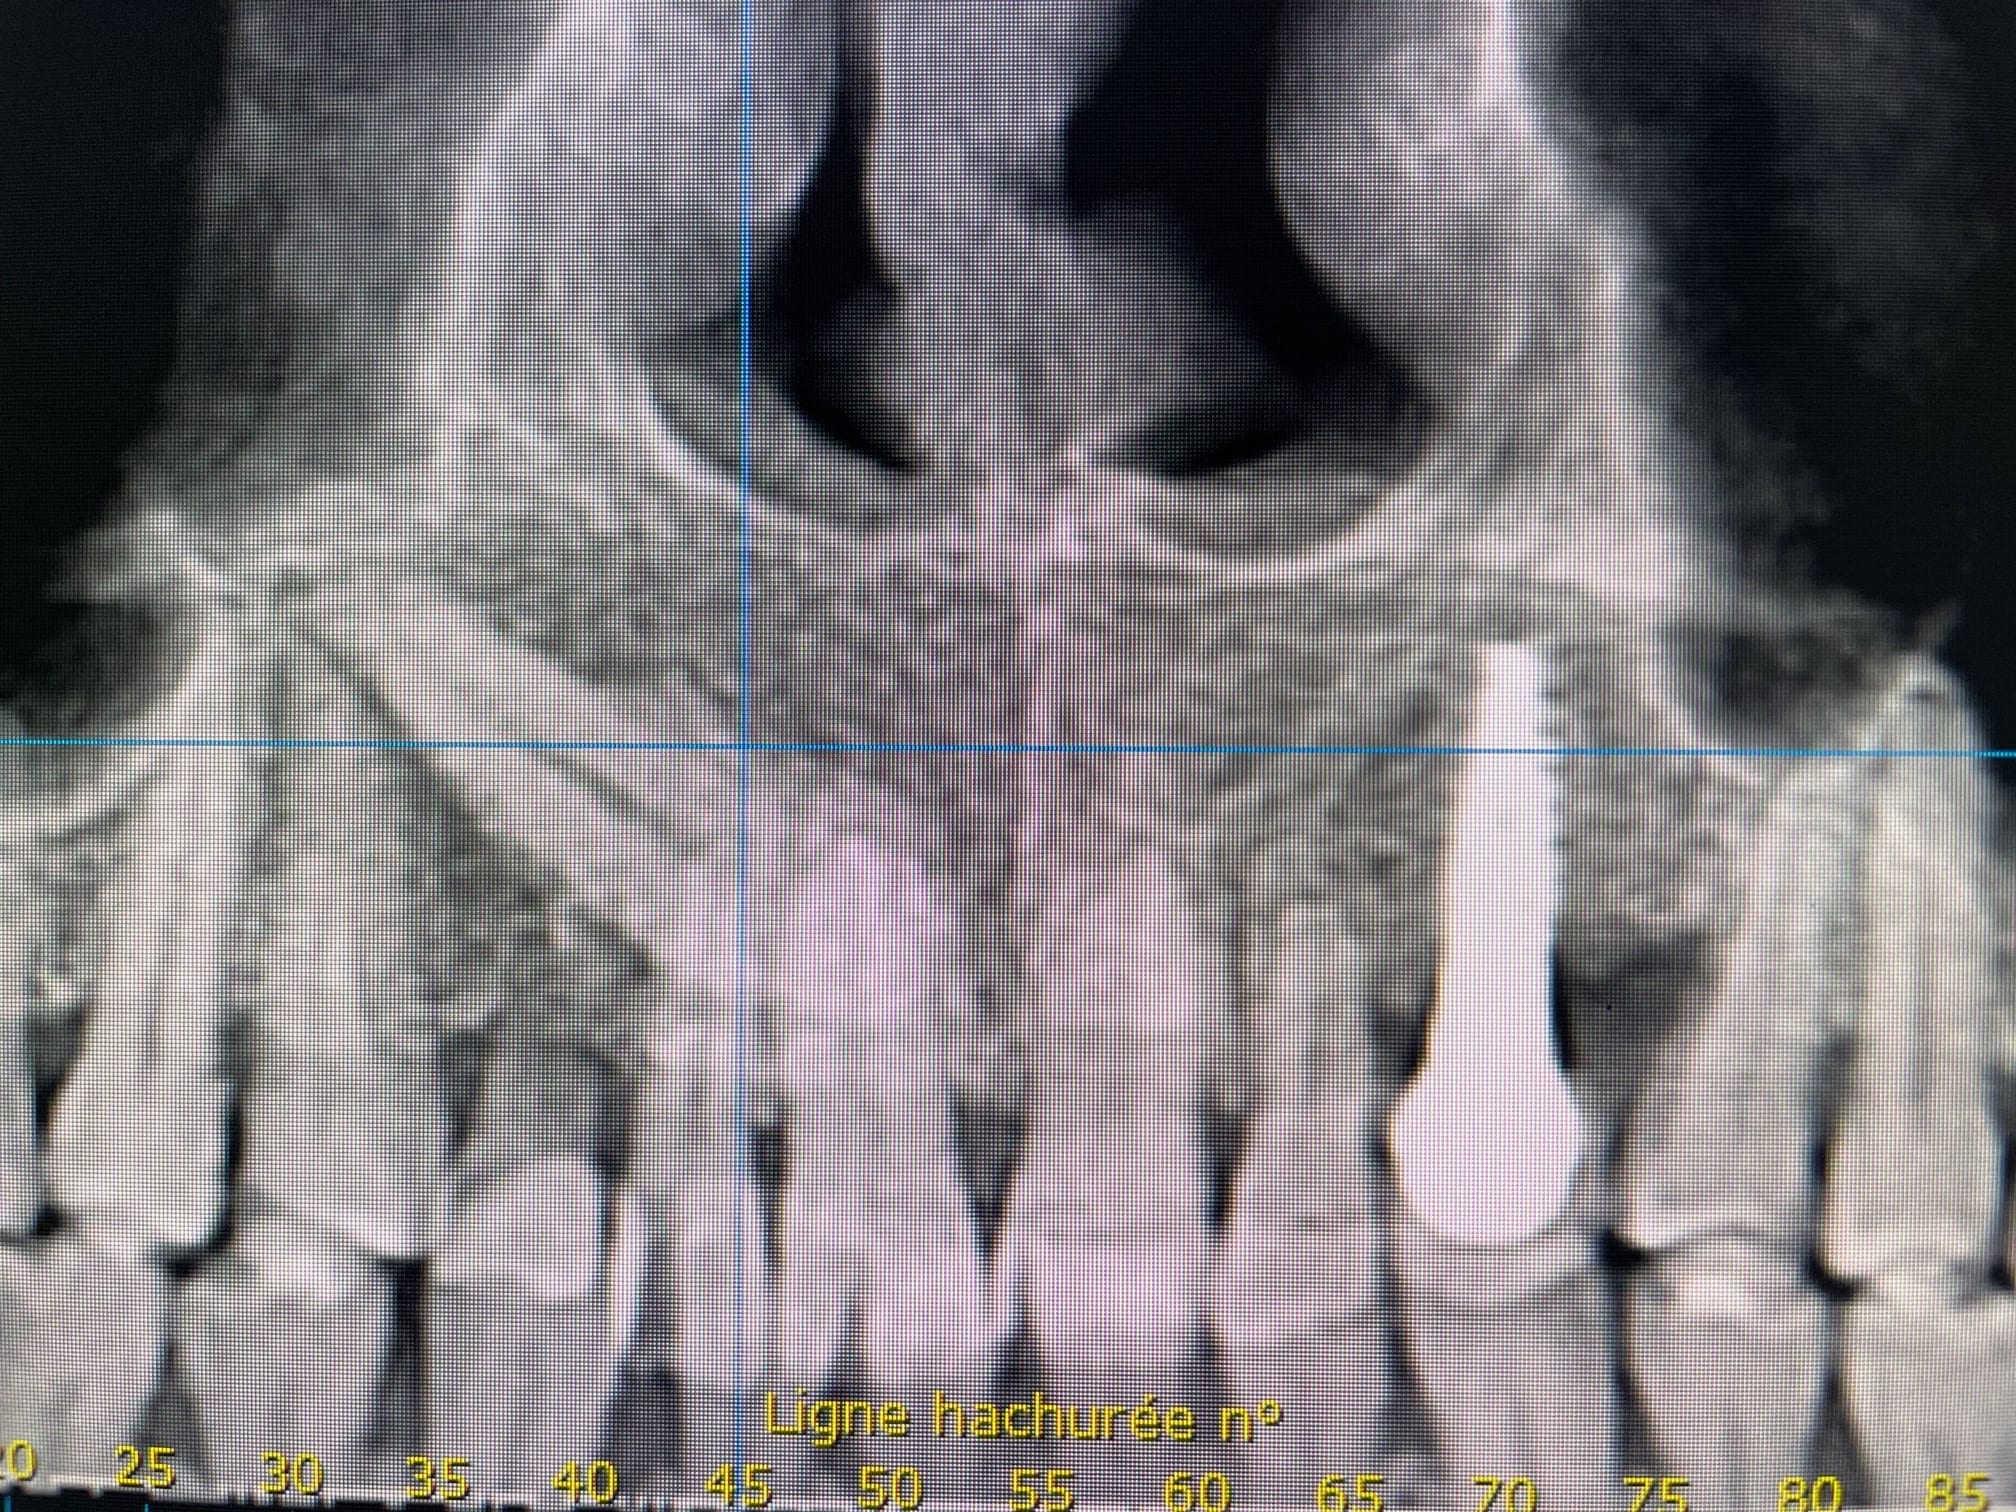

Que pensez vous de cette canine incluse? J'hésite à me lancer pour l'extraire avant d'implanter ou alors de la transfixer comme le fait Davarpannah.

J'ai vu Pluton que tu avais eu des échanges avec notre confrère Thierry Degorce à ce sujet sur un autre blog. ^^